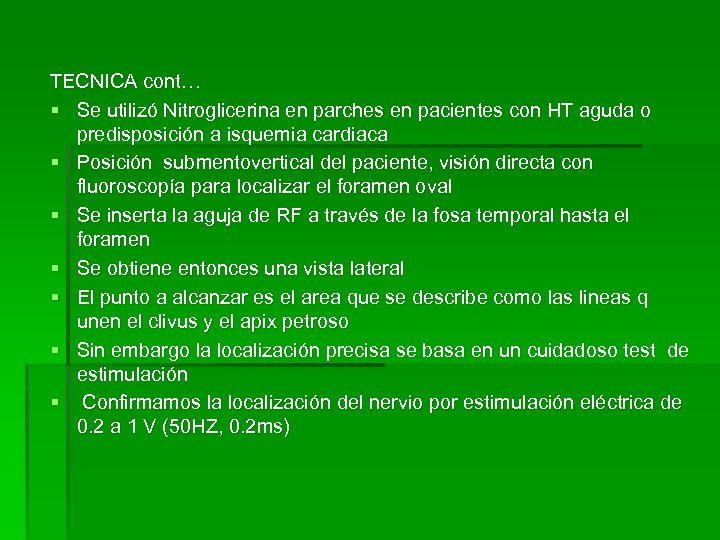

TECNICA cont… § Se utilizó Nitroglicerina en parches en pacientes con HT aguda o predisposición a isquemia cardiaca § Posición submentovertical del paciente, visión directa con fluoroscopía para localizar el foramen oval § Se inserta la aguja de RF a través de la fosa temporal hasta el foramen § Se obtiene entonces una vista lateral § El punto a alcanzar es el area que se describe como las lineas q unen el clivus y el apix petroso § Sin embargo la localización precisa se basa en un cuidadoso test de estimulación § Confirmamos la localización del nervio por estimulación eléctrica de 0. 2 a 1 V (50 HZ, 0. 2 ms)

TECNICA cont… § Se utilizó Nitroglicerina en parches en pacientes con HT aguda o predisposición a isquemia cardiaca § Posición submentovertical del paciente, visión directa con fluoroscopía para localizar el foramen oval § Se inserta la aguja de RF a través de la fosa temporal hasta el foramen § Se obtiene entonces una vista lateral § El punto a alcanzar es el area que se describe como las lineas q unen el clivus y el apix petroso § Sin embargo la localización precisa se basa en un cuidadoso test de estimulación § Confirmamos la localización del nervio por estimulación eléctrica de 0. 2 a 1 V (50 HZ, 0. 2 ms)